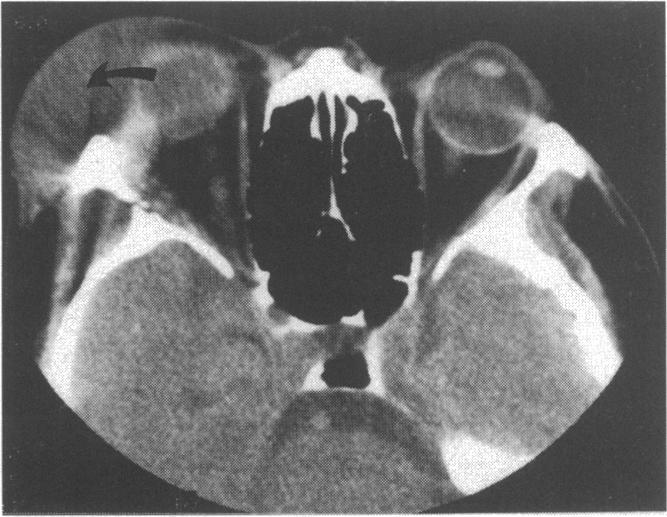

Orbital coccidioidomyosis presenting as a lacrimal gland fossa mass.

Br J Ophthalmol. 1995 Dec;79(12):1145-6. doi: 10.1136/bjo.79.12.1145.